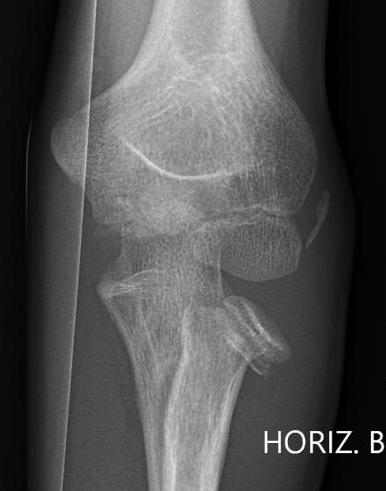

Xray

Radial neck fracture and olecranon fracture